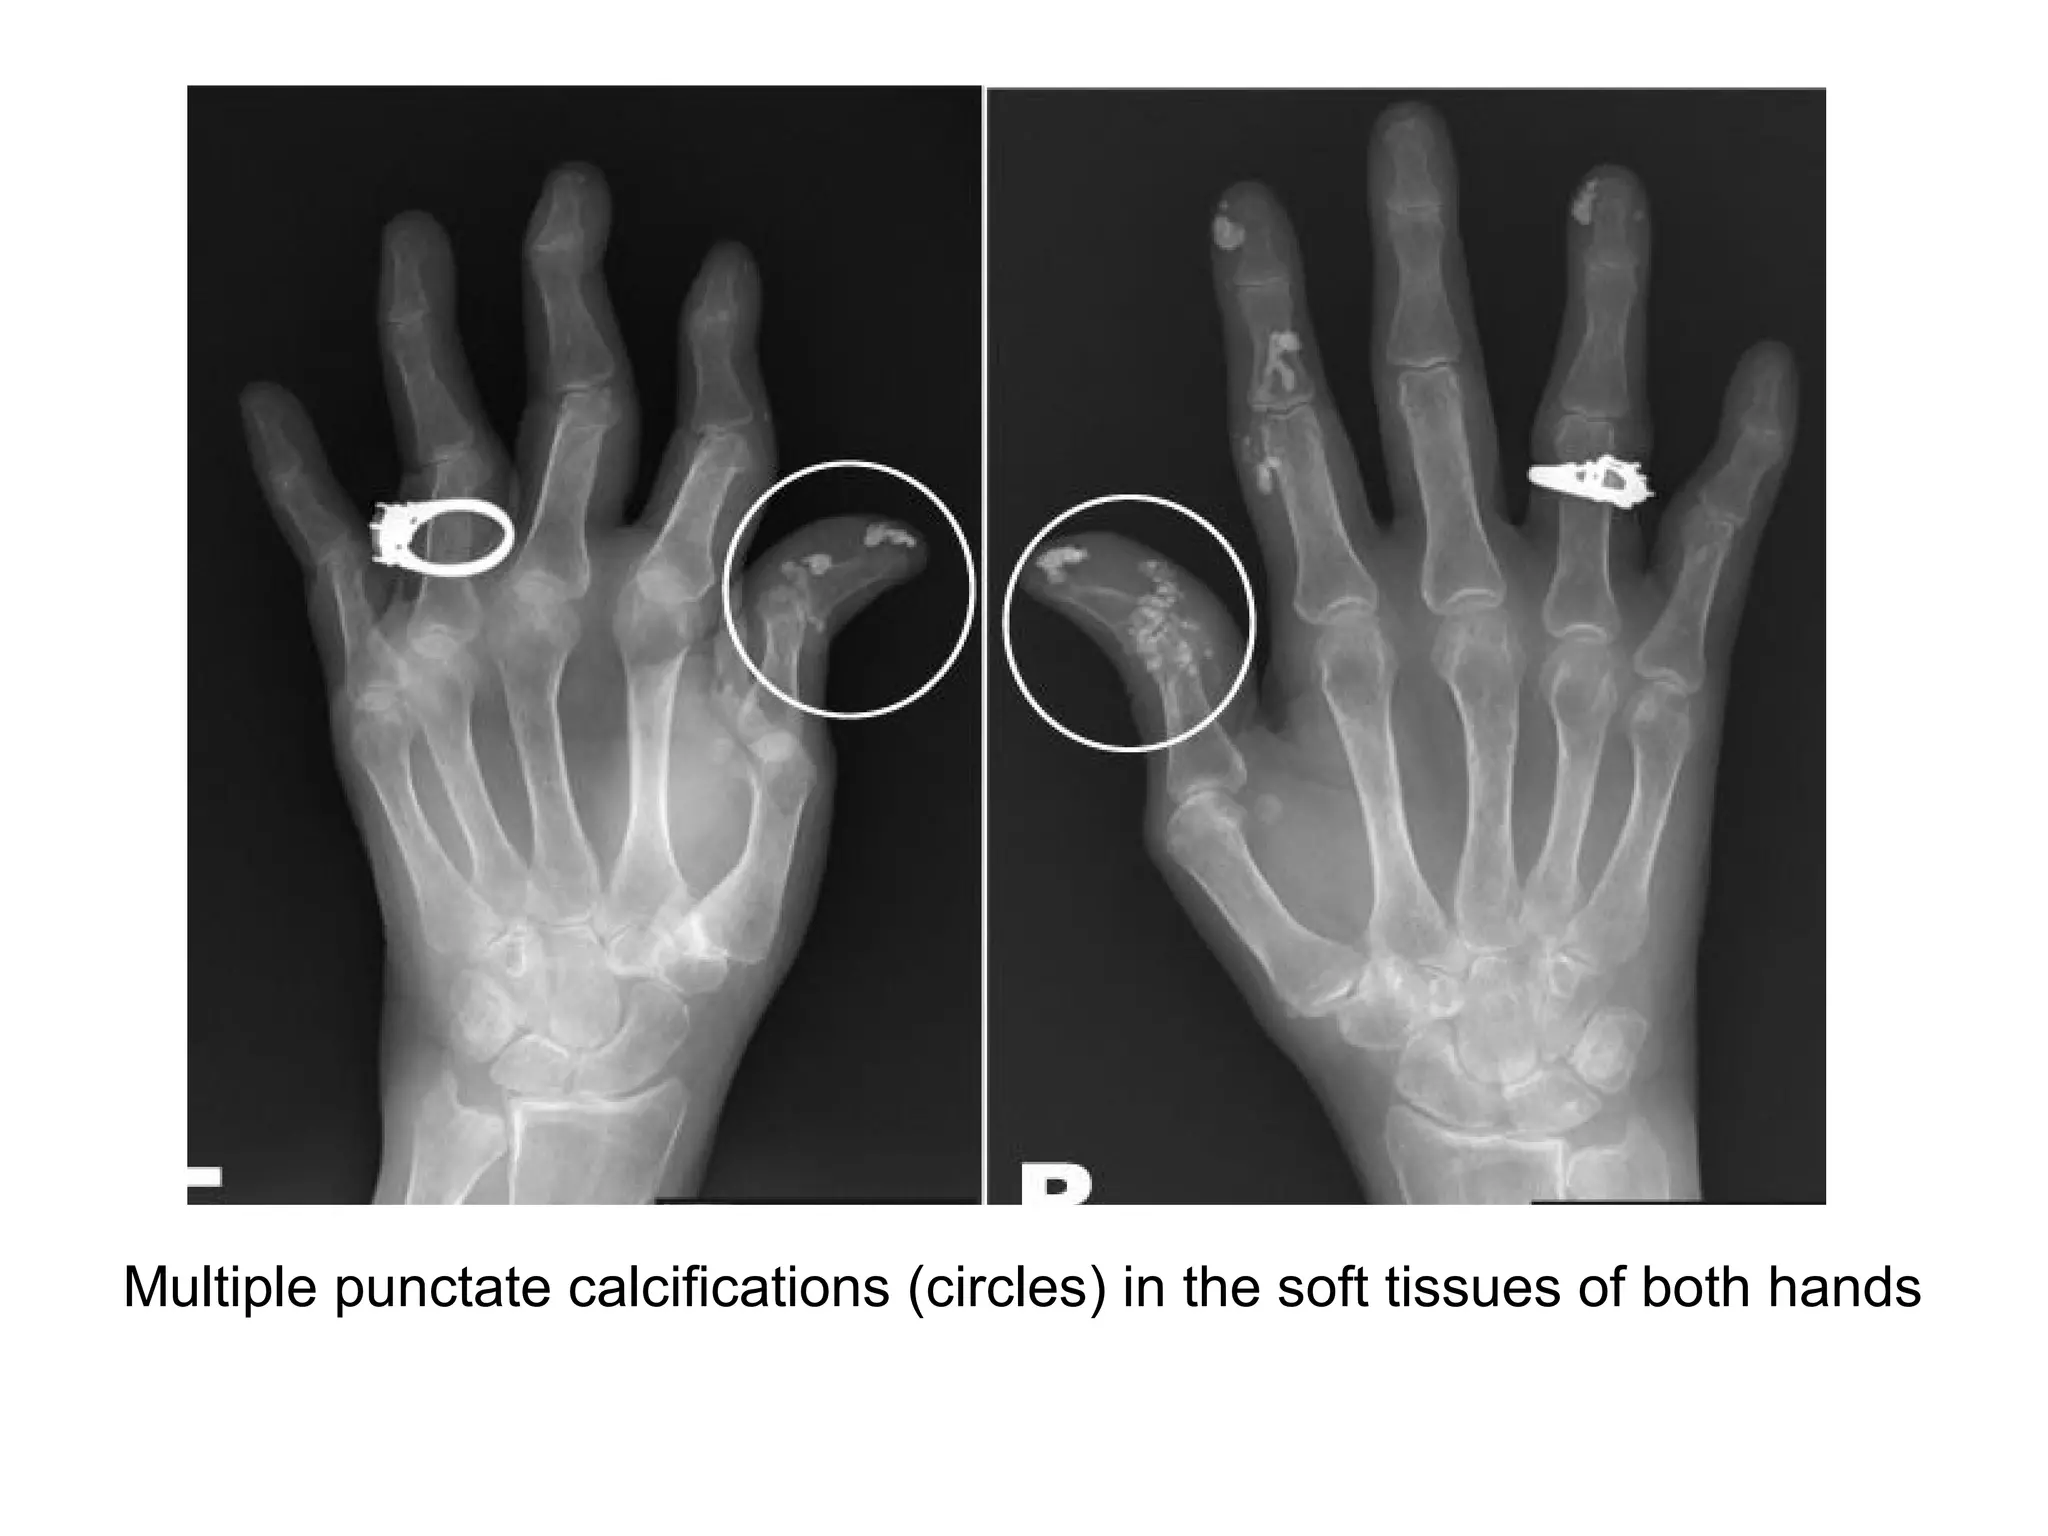

Multiple punctate calcifications (circles) in the soft tissues of both hands

b) Radiographic Features :

-Imaging findings demonstrate bone and soft tissue

changes

-The hands (finger tips) are the most common site of

involvement

1-Bone changes :

-Acro-osteolysis (resorption of the distal portion of the distal

phalanges) is characteristic , especially if there is

accompanying calcification

-Periarticular osteoporosis

-Joint space narrowing

-Erosions

2-Soft tissue Changes :

-Subcutaneous and periarticular calcification

-Atrophy especially at tips of fingers

-Flexion contractures